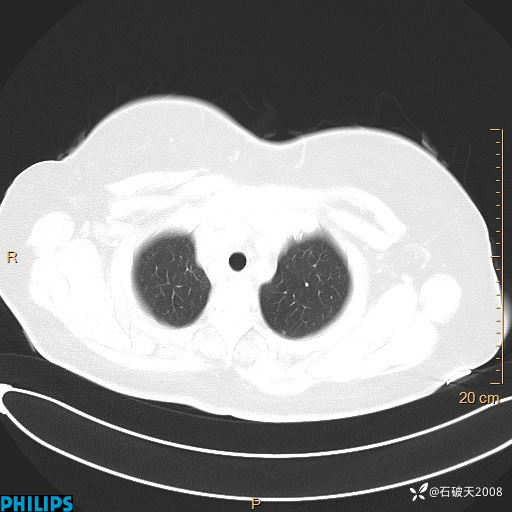

肺结节病?纵膈型肺癌?淋巴瘤?有点意思,欢迎围观

女 52岁 主 诉:咳嗽10余天,咳痰2天。

现病史:10余天前无明显诱因出现咳嗽,呈阵发性干咳,伴咽喉部发痒,无咽痛,无咳痰,无鼻塞、流涕、打喷嚏,无发热、畏寒、寒颤,无头痛、头晕,无胸闷、胸痛,无反酸、烧心,无腹痛、腹泻,无尿频、尿急,无皮疹等,在当地诊所求治,给予口服药物治疗(具体不详),病情无好转。遂在当地社区卫生服务中心开具口服药物治疗(具体不详),疗效欠佳。2天前出现咳痰,在我院门诊求治,行胸部CT提示肺部感染,建议住院,患者要求口服药物治疗,目前仍咳嗽、咳白色粘痰,白天量多,夜间自觉喉部喘鸣音,遂再次来院就诊,以“肺部感染”为诊断收入院。发病以来,神志清,精神可,饮食可,夜间睡眠差,大小便正常,近期体重无明显变化。

肺窗